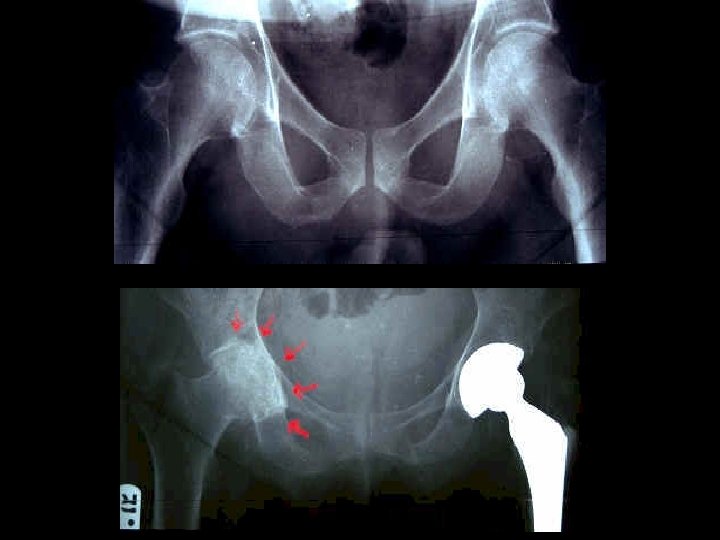

ASSESSMENT • For many plain radiograph remains the best means of assessment: – Evidence of cartilage loss (joint space narrowing) – Bone response (osteophytes and sclerosis) • There is often considerable discordance between structural change and clinical outcome

SURGERY • JOINT REPLACEMENTS • ARTHROSCOPIC LAVAGE • OSTEOTOMY • ARTHRODESIS